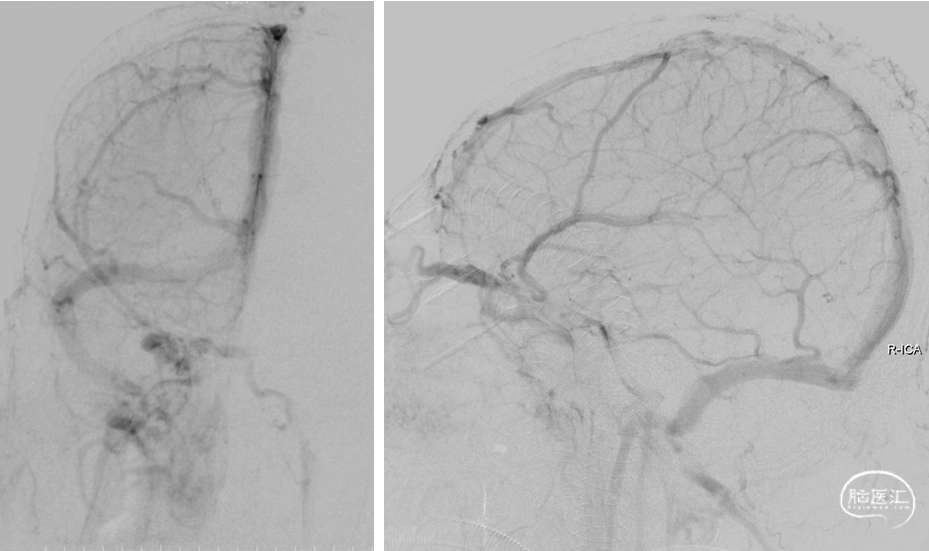

DSA(2022-1-6)

右侧颈总动脉造影示:上矢状窦显影模糊,右侧横窦、乙状窦未见显影,静脉回流缓慢。穿刺右侧颈静脉,留置8F血管鞘,全身肝素化,50万尿激酶入动脉滴注。